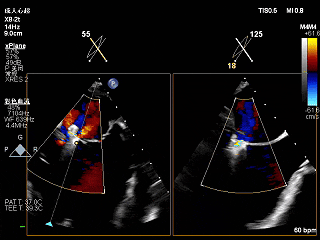

3D-ZOOM 彩色多普勒显示反流主要来源于2区

2维上彩确认夹子位置

夹子关小后二维上彩,夹子两侧均有反流

夹子关紧后上彩

夹子关小后3D上彩

反流降至轻度

夹子释放后,2D下color,反流降至轻度